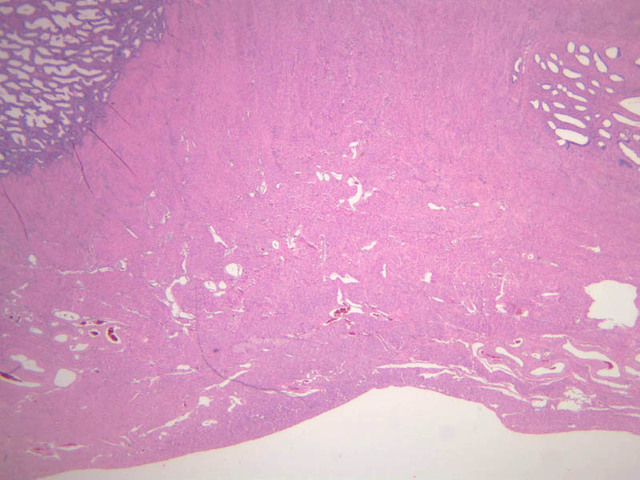

The uterus is a pear-shaped muscular organ, somewhat flattened from front to back. The expanded upper portion is referred to as the fundus, while its lower part, which protrudes into the vagina, is called the cervix. The lumen of the uterus is slit-like and is in communication with that of the uterine tubes (B-97, monkey uterus [1x, 1x, 1x, 1x]). The wall of the uterus consists of three layers: perimetrium, myometrium, and endometrium (B-97 [1x, 1x-labeled] [1x, 1x, 1x]; B-100 [1x, 1x]). The perimetrium is peritoneum which covers the uterus, but is lacking in the posterocaudal third below the peritoneal reflection (B-97 [2.5x, 10x, 20x, 40x]). The myometrium is the very thick middle layer consisting of bundles of smooth muscle cells arranged into several interwoven layers (slide B-93 [1x-labeled, 2.5x] [1x, 2.5x] [1x, 2.5x] [2.5x, 10x, 20x, 40x]). The endometrium is the innermost layer and is a glandular mucosa (B-97 [2.5x, 10x, 20x] [2.5x, 10x, 20x] [2.5x, 10x, 20x, 40x]). It consists of a surface epithelium which is invaginated into tubes called uterine glands. The glands penetrate into a very thick lamina propria referred to as the endometrial stroma. The surface epithelium is a mixture of ciliated and non-ciliated simple columnar cells, whereas the glandular epithelium consists mainly of non-ciliated secretory cells. The endometrial stroma has the appearance of a loose, rather cellular mesenchyme with numerous blood vessels.

The endometrium is subdivided into two main parts; the basalis and the functionalis (slide B-97). The basalis is deep, lying adjacent to the myometrium, it consists of stroma and the closed ends of the uterine glands and is not sloughed during menstruation. The functionalis is upper zone consisting of the remainder of the uterine glands with intervening stroma. It is lost during menstruation, but is replaced again with each menstrual cycle, by proliferation of the persisting elements in the basalis.

The menstrual cycle is a continuous series of events, dominated by the endocrine activity of the ovary, which repeats itself with a 28 day period. The endometrium participates by undergoing a series of structural changes which are roughly divided into three categories, the proliferative, secretory, and menstrual phases. These phases are listed below, examine each of the uterine slides and determine to which phase it belongs.